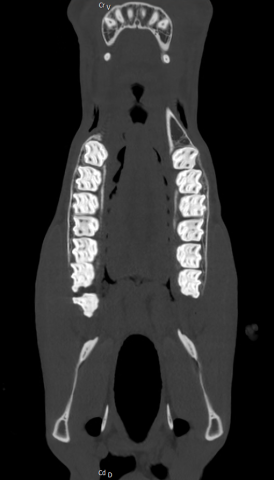

Oberkiefer CT mit Polydonti